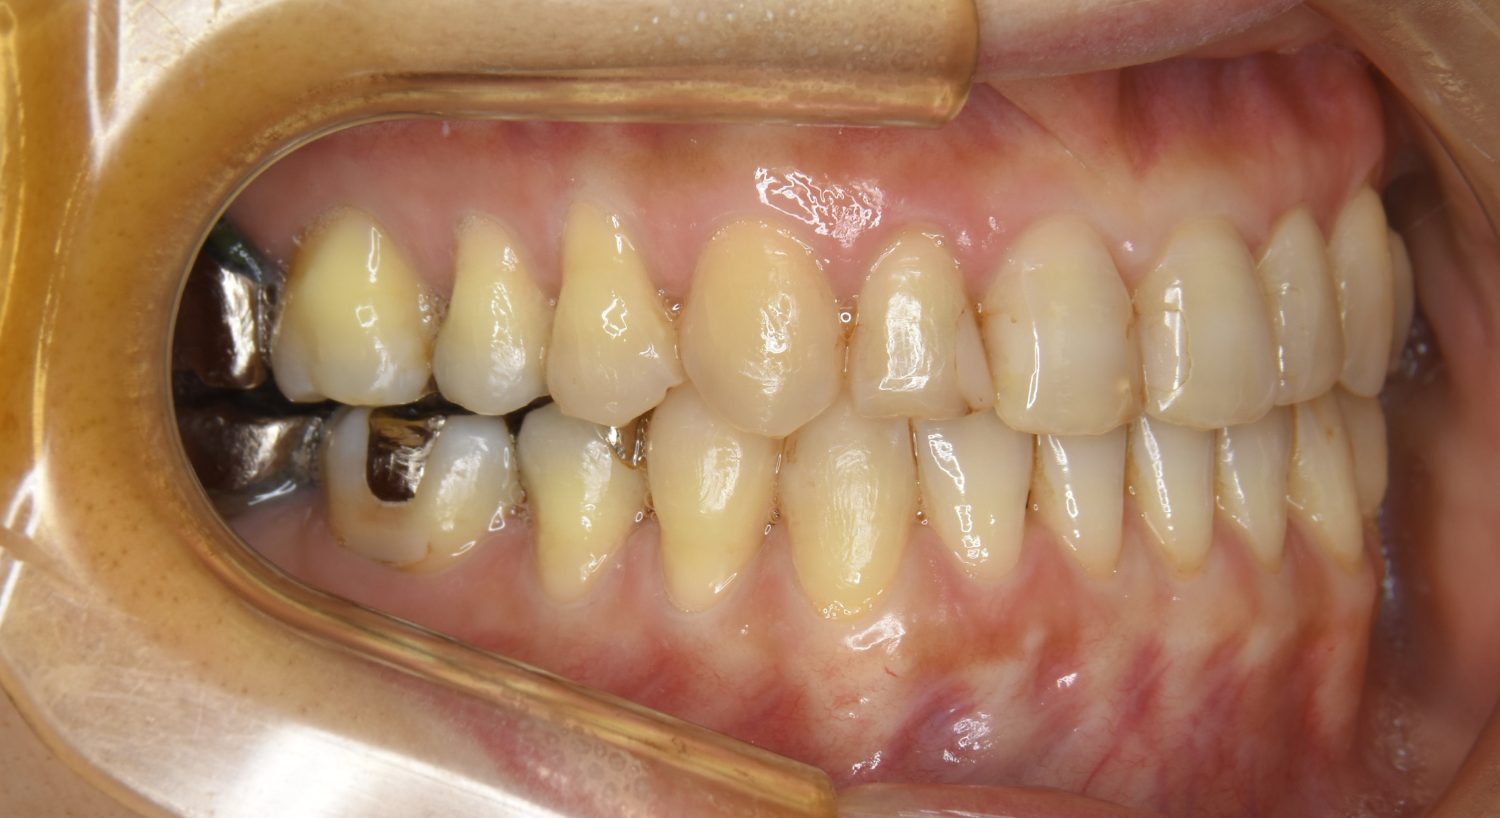

叢生の症例紹介②

Before

After

主訴

歯の凸凹を治したい。

治療内容

アライナー(インビザライン)にて非抜歯で治療を行いました。

上下前歯部に叢生(凸凹)が認められる状態でした。歯列の遠心移動を行うことで機能面および審美面が改善されました。